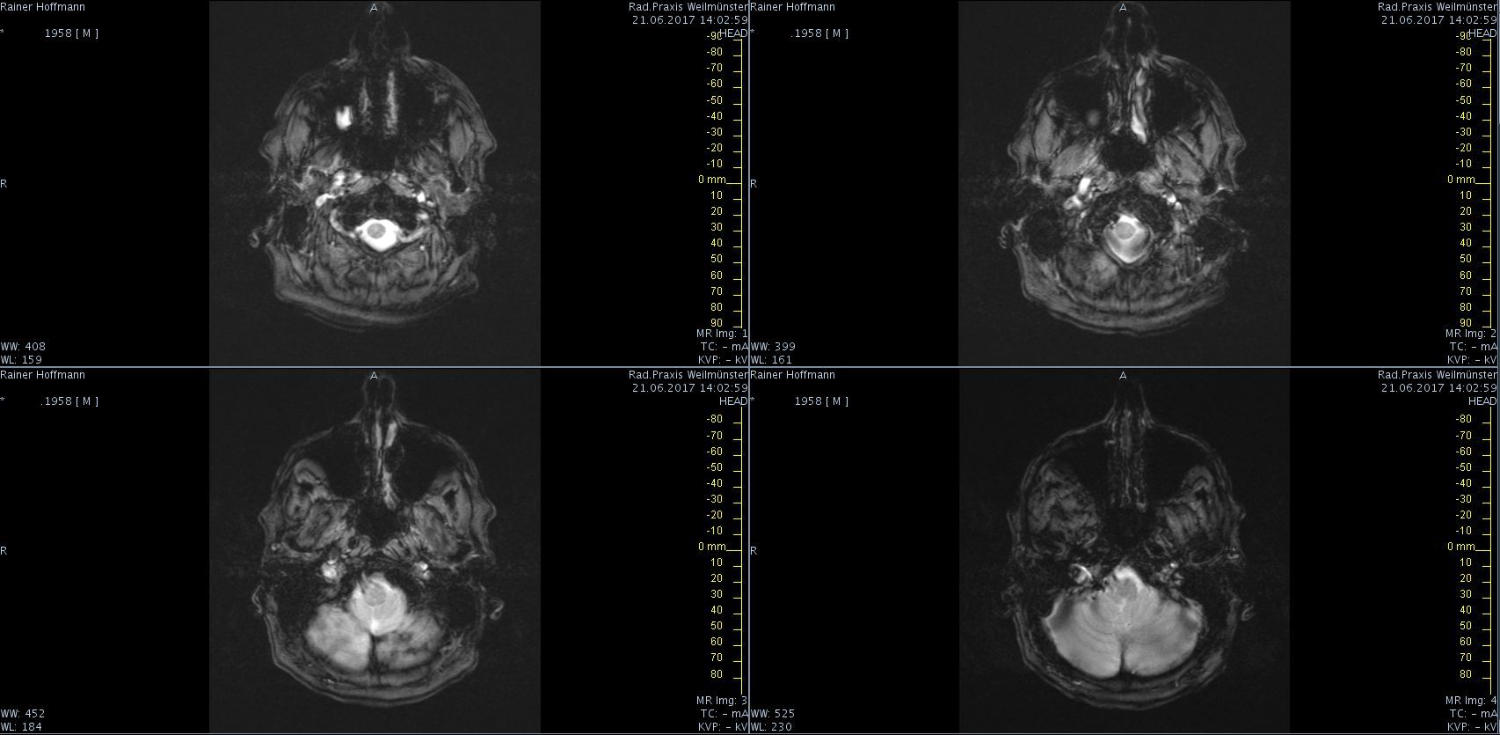

Das ist ja ganz toll, dass Ihr die Seite so schnell gefunden habt. Ich zeige euch jetzt ein ganz, ganz anderes Paßfoto von mir. Es könnte Ähnlichkeiten zu anderen lebenden oder bereits verstorbenen Personen geben. Wenn Ihr das erste Bild oben links anklickt wird es ver- größert dargestellt. Dann kann man mit den Pfeiltasten am unteren Bild- rand durch meinen Kopf blättern. Es gibt nicht viel zu sehen. Vielen Dank an Martina für Ihre Hilfe.

MRT